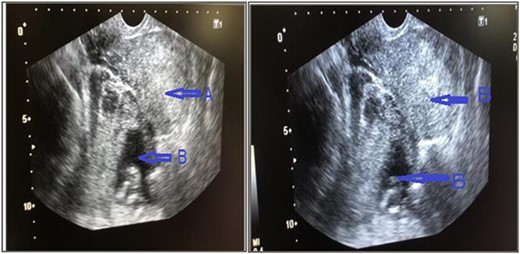

The patient was taken to the operating room (OR) without delay. She underwent an emergent exploratory laparotomy under general anesthesia and an ectopic pregnancy at the left adnexa, implanted at the broad ligament attached with left ovary and fallopian tube, and hemoperitoneum of ~50 ml was noted. Dissection was made to free the left ovary and the mass including the placenta and gestational sac and the fetus measured ~10.8 × 13 cm, (Fig. 2) was removed alongside left fallopian tube. A dead fetus of 150 gms (Fig. 3) was later extracted from the gestation sac.

Ectopic pregnancy at the left adnexa, extending to occupy the left broad ligament, left ovary was attached on it but dissectable, size ~10.8 cm, placenta and sac together.